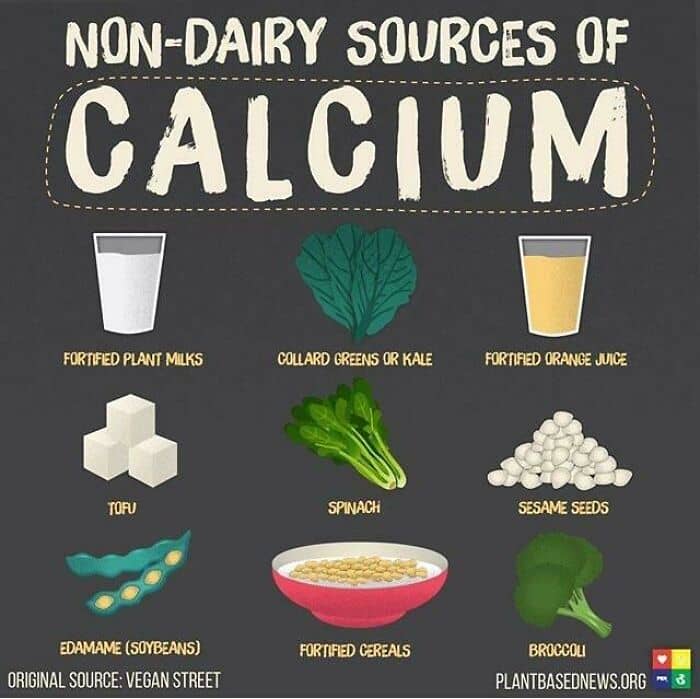

That you can lose all your teeth during pregnancy because if you’re not taking enough calcium rich foods, your foetus can take all the calcium from your teeth.

I actually saw a case like that on the internet.